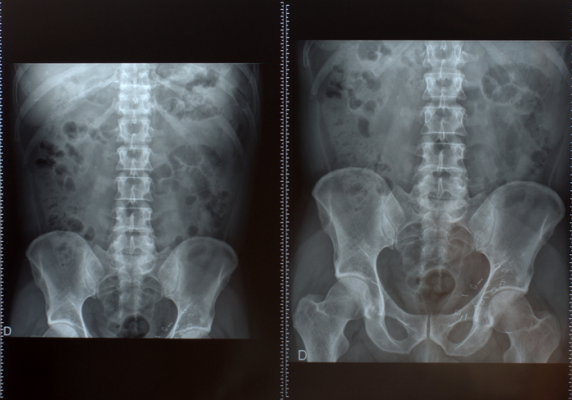

Organized by RSNA in collaboration with the American Society of Emergency Radiology (ASER) and the Society for Abdominal Radiology (SAR), the challenge gave researchers the task of building artificial intelligence (AI) models that detect severe injury to the internal abdominal organs, as well as any active internal bleeding.

The latest in a series of research competitions that RSNA has conducted since 2017, the RSNA Abdominal Trauma Detection AI Challenge represents the Society’s most ambitious AI challenge to date, encompassing detection and classification of traumatic injuries across multiple organs, including the liver, spleen, kidneys, and bowel. The international imaging dataset is the first multiphasic dataset that RSNA has assembled for a challenge and is one of the largest and most varied of its kind, including detailed clinical labels, radiologist annotations and segmentations.

“The dataset is annotated at multiple levels, including the presence of injuries in four solid organs with injury grading, image level annotations for active extravasations and bowel injury, and voxelwise segmentations of each of the potentially injured organs,” said Jeff Rudie, M.D., Ph.D., emergency radiologist and Scripps Clinic and adjunct assistant professor in the Department of Radiology at the University of California, San Diego.

To create the ground truth dataset, the challenge planning task force collected imaging data sourced from 23 sites in 14 countries on six continents, including more than 4,000 CT exams with various abdominal injuries and a roughly equal number of cases without injury.

Nearly 5 million people die each year as a result of traumatic injury, according to the World Health Organization. Abdominal trauma often causes damage to the internal organs, which may result in internal bleeding and injuries to the kidneys, spleen, liver and bowel. Rapid and accurate detection and classification of injuries is key to effective treatment and favorable patient outcomes.